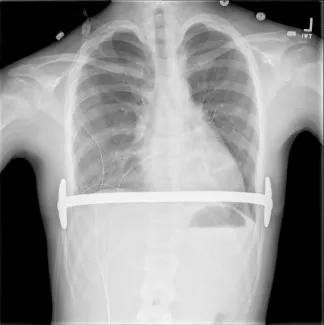

Repair with a metal pectus bar, called the Nuss Procedure, is achieved by bending a stainless bar to fit the chest wall. The bar is then inserted and secured through a small incision under each arm using the aid of a endoscope to monitor and avoid injury to the heart during insertion. The bar goes over the ribs and under the sternum, to push the sternum forward into the new position. The ends of the bar are secured to the chest wall. This procedure takes between 1–2 hours.

Patients who have a Ravitch procedure without a chest strut are seen only as needed after the first postoperative appointment. Ravitch procedure patients with a chest strut or Nuss procedure patients with a bar are seen at least annually after the first visit. The strut or bar is expected to stay in place for 2-3 years.

- Sports may be resumed as soon as the surgeon determines this is safe. Some contact sports may be not be permitted while the bar is in place. The bar may prevent adequate chest compressions during CPR and defibrillation requires paddle adjustment to be effective.

- No MRI should be done while the Pectus bar in in place.

- Use of a medical alert bracelet or necklace is recommended at all times in order to notify emergency providers of the presence of a Pectus bar. Recommended bracelet text: Steel bar in chest. CPR more force. Cardioversion ant/post paddle placement.